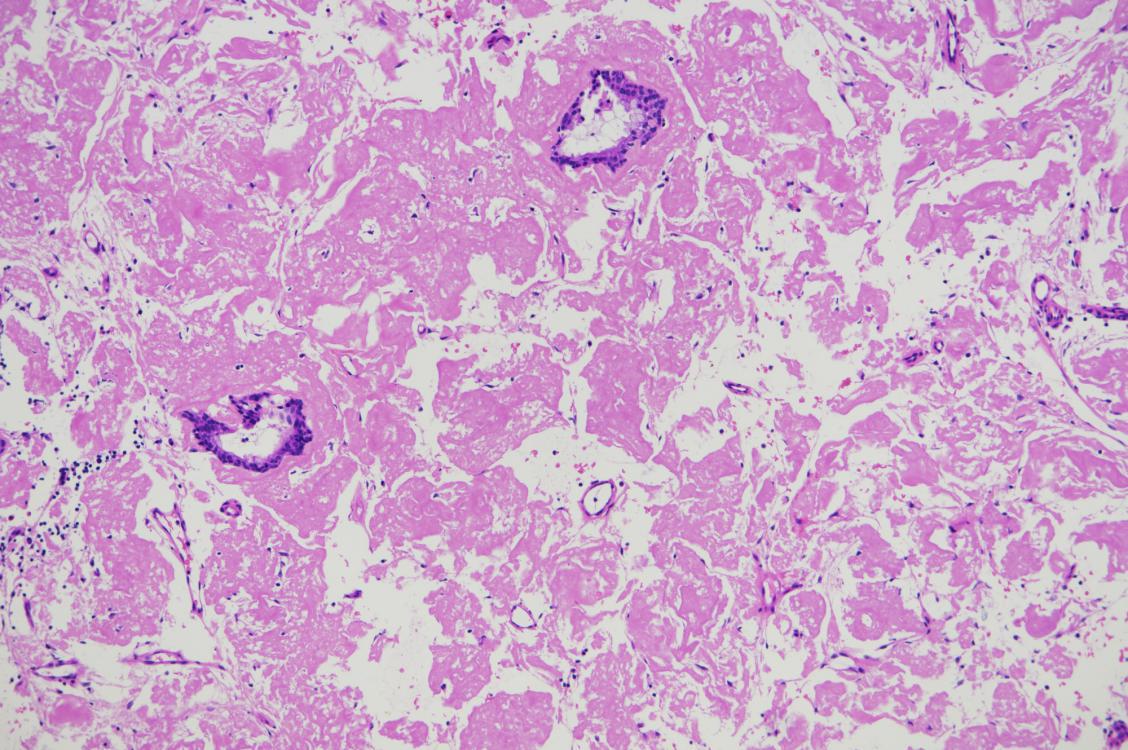

1.(支气管)见较多嗜伊红物质,散在粘膜上皮细胞,待特染助诊。

2.补充报告(2015-10-16):(支气管)破碎粘膜上皮伴弥漫性淀粉样物质沉着。见图5

3.免疫组化(2015-N16002):15S32397-001:CK7(上皮+),CD68(组织细胞+),TTF-1(上皮+),P63(部分上皮细胞+)

4. 特染:刚果红(+),见图6,网染(示网状纤维较少),AB(-),PAS(-)

图5

图6